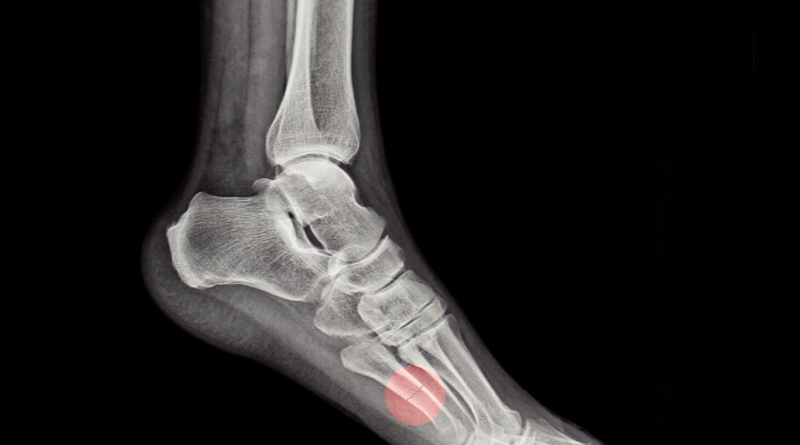

통풍은 혈액내에 요산의 농도가 높아지면서 요산염 결정이 관절과 연골, 힘줄 주위 조직이 침착되는 질병입니다.

통풍은 바람만 스쳐도 극심한 통증을 느끼는 질병입니다.